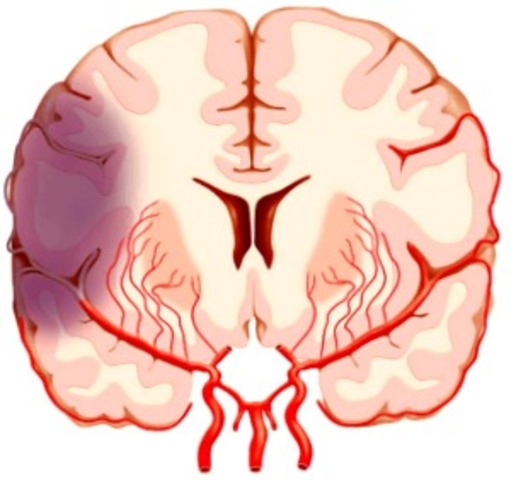

El patrón de la isquemia global refleja la disposición anatómica de los vasos sanguíneos cerebrales y la sensibilidad de los distintos tejidos cerebrales a la falta de oxigeno.

La disposición anatómica de los vasos sanguíneos cerebrales predispone al desarrollo de dos tipos de lesión.

Zonas anatómicamente vulnerables situadas entre territorios superpuestos irrigados por las arterias cerebrales mayores.

*La Hipotension marcada -------> La irrigación sanguínea de zonas distales disminuye, lo que predispone a la isquemia y al infarto de los tejidos.

Tiene lugar en regiones irrigadas por las arterias penetrantes.

La sustancia gris de la corteza esta irrigada por este tipo de arterias que van a formar una cascada a medida que se ramifican repetidamente para dar lugar a una red capilar. Un descenso brusco de la presión arterial reduce significativamente el flujo sanguíneo a lo largo de esto conductos capilares.